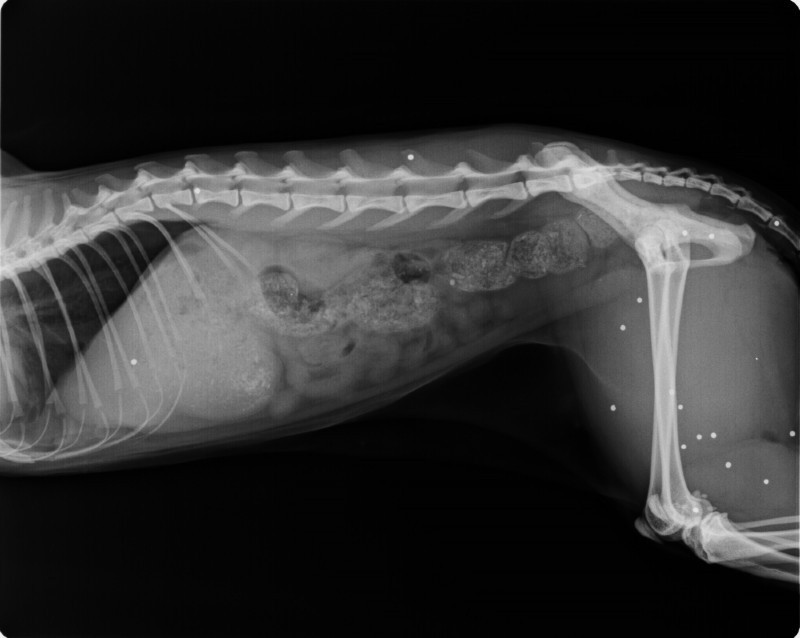

Ultraschall

- Abdominalultraschall